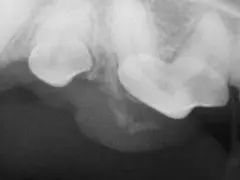

Figure 2. Radiograph of the effected area, showing soft tissue mineralization associated with the tumor.

Under anesthesia, a dental radiograph (Figure 2) was obtained which showed a partially mineralized soft tissue mass. It was not clear from which tooth the mass was emanating. A segmental maxillectomy with approximate 5-10 mm margins was performed. The resected tissues included the first and second premolars along with all associated periodontal structures. Picture 3 shows the patient after the complete resection and prior to closure. Note that the resected area of the maxilla extended across the palate and the nasal turbinates were exposed. Figure 4 shows the site after closure.